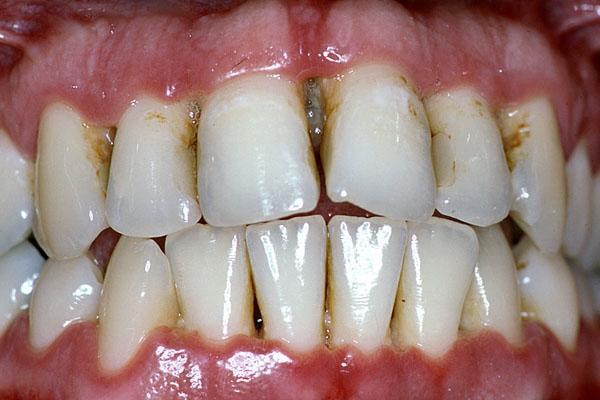

Parodontitin əsas əlamətləri bunlardır:

- Diş ətində şişkinlik və qızartı

- Diş ətində qanamağa meyllilik

- Dişlərin laxlaması

- Diş ətlərində çəkilmə